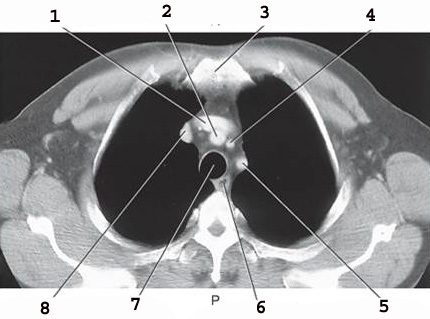

1

Left brachiocephalic vein

2

Braciocephalic Artery

3

sternum

4

L Common carotid A

5

Left subclavian Artery

6

Esophogus

7

Trachea

8

RT brachiocephalic vein (page 325)